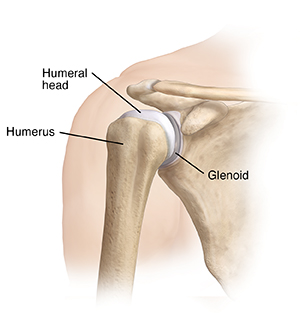

A healthy, stable shoulder

The head of the arm bone (humerus) rests in a socket (glenoid), much like a golf ball fits on a tee. Parts of the joint called stabilizers hold the humeral head and glenoid together. These include a sheet of ligaments and other tough fibers called the capsule. This encloses the humeral head and glenoid.